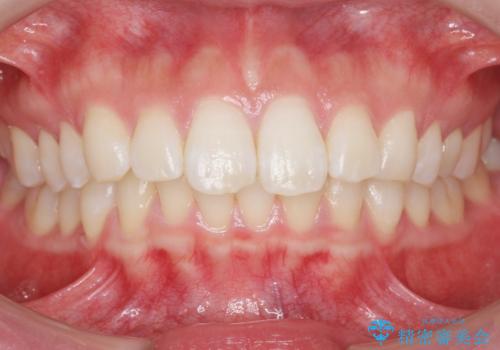

被せ物がはずれたまま放置していた 20代女性

- 以前つけた被せ物がすぐにはずれてしまい1年以上放置してしまったことを主訴に来院された患者様です。

自然な仕上がりにご満足頂けました。

「うわー、自分の歯みたい!すごい!」と喜んで下さいました。

ホワイトニングも行い、口元の印象が明るくなりました。